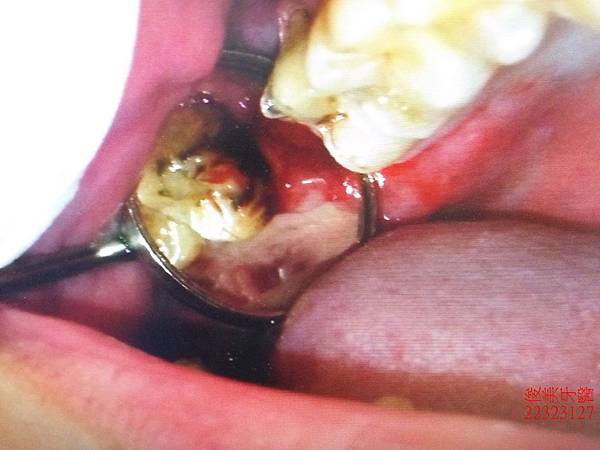

患者於就醫時表示:想要補蛀牙,經醫師檢查後發現,患者的右上最後一顆牙齒,早已填補過,

但因容易塞東西,且患者清潔不良導致牙齒頰側及後方變黑,填補並非杜絕蛀牙的良方。

打開後取出一些發炎組織。